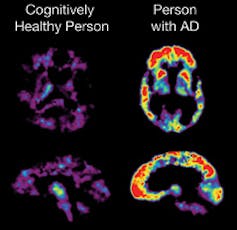

Though the effect of aducanumab, the Alzheimer’s drug developed by biotechnology company Biogen, on hard clinical endpoints are lackluster[12], it has been shown to reduce the formation of amyloid beta plaques[13] in patients with early-stage Alzheimer’s. Amyloid beta[14] denotes proteins that clump together to form plaques commonly seen in patients with Alzheimer’s. It’s been hypothesized that these plaques drive the signs and symptoms of Alzheimer’s. Animal models[15] have shown that interfering with amyloid beta plaque formation could lead to improvements in functioning.

The data linking amyloid beta plaques to hard clinical endpoints is not a slam-dunk. Unlike hypertension[17] and elevated LDL cholesterol[18], which has been proved to be linked to cardiovascular events, amyloid beta[19] has not seen such definitive results.

The role of amyloid beta plaques in Alzheimer’s disease is still debated among scientists.Was the FDA’s ruling a mistake?